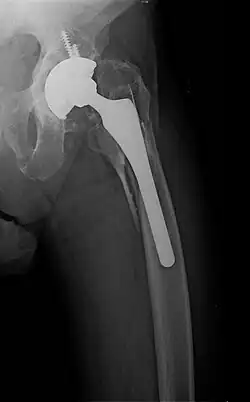

![]() | |

| Internal and external views of an arm with a compound fracture, both before and after surgery | |

A bone fracture (abbreviated FRX or Fx, Fx, or #) is a medical condition in which there is a partial or complete break in the continuity of any bone in the body. In more severe cases, the bone may be broken into several fragments, known as a comminuted fracture.[1] An open fracture (or compound fracture) is a bone fracture where the broken bone breaks through the skin.[2]